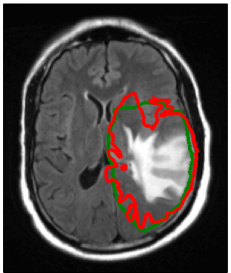

Refer to caption

(a) 3.5 month

(b) 7.5 months

Figure 7: T2-FLAIR images acquired after therapy, overlaid with isolines of the tumor cell density simulated on the diagnostic images prior to radiotherapy (figure 3a): (a) 3.5 month after diagnosis with isolines for tumor cell densities of 101superscript10110^{-1}, 102superscript10210^{-2}, and 103superscript10310^{-3}, and (b) 7.5 months after diagnosis with isolines for tumor cell densities of 102superscript10210^{-2}, 103superscript10310^{-3}, and 104superscript10410^{-4}.

5.3 Comparison of follow-up images and simulated tumor infiltration

By considering the delivered dose distribution in figure 6d, we see that the progressive tumor is located almost entirely within the high dose region receiving approximately 60 Gy. Under the assumption that a radiation dose of 60 Gy kills a fraction of the tumors cells, the shape of the isolines after therapy is not altered within the high dose region. In this case, the Fisher-Kolmogorov model predicts that the progression of the tumor approximately follows the isolines of the tumor cell density simulated pre therapy. This motivates to compare the simulated cell density isolines directly to the follow-up images without explicitly modeling the effect of chemoradiation on the cell density quantitatively.

In figure 7 we overlaid the tumor cell density simulated on the diagnostic image on the follow-up T2-FLAIR images. It is seen that the progression of the tumor post therapy follows the isolines of the simulated tumor cell density relatively closely. In particular, the follow-up images show the progression of the tumor through the corpus callosum into the contralateral hemisphere as predicted by the model. The latter is supported by the T1 post contrast images 3.5 and 7.5 months post therapy, which show contrast enhancement in the corpus callosum (T1 images not shown).